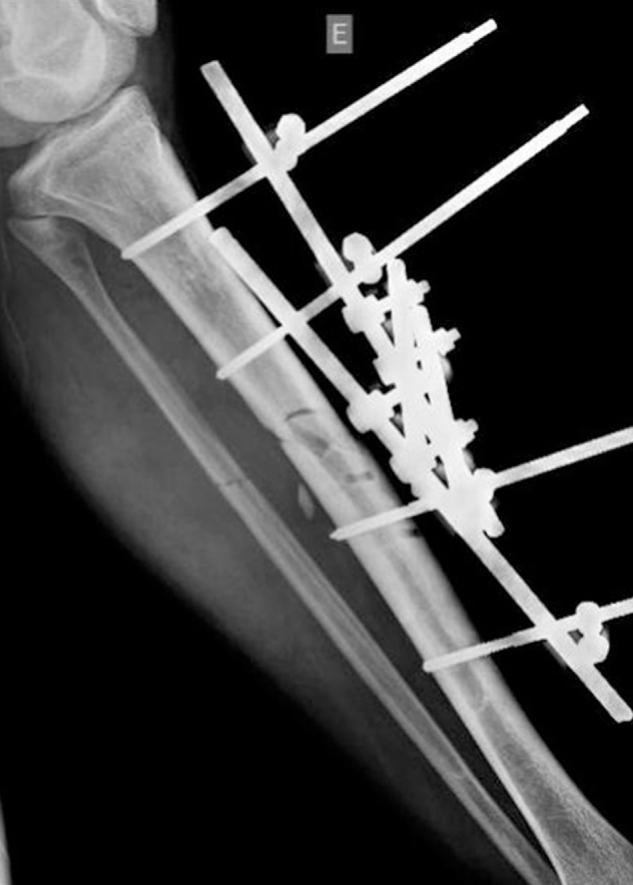

接受外固定治疗的骨科损伤患者的术后感染

Postoperative infection in patients undergoing inspection of orthopedic damage due to external fixation.

To conduct a retrospective analysis on cases undergoing inspection of orthopedic damage, at an orthopedic emergency service in a teaching hospital, with the aim of evaluating patients with postoperative infection after conversion to internal osteosynthesis.

This was a retrospective analysis covering the period from June 2012 to June 2013, on patients who underwent inspection of orthopedic damage due to external fixation and subsequently were converted to definitive osteosynthesis using a nail or plate.

We found an infection rate of 13.3% in our sample and, furthermore, found that there had been technical errors in setting up the fixator in 60.4% of the cases.

We found an infection rate that we considered high, along with inadequacies in constructing the external fixator. We emphasize that this procedure is not risk-free and that training for physicians who perform this procedure should be mandatory.